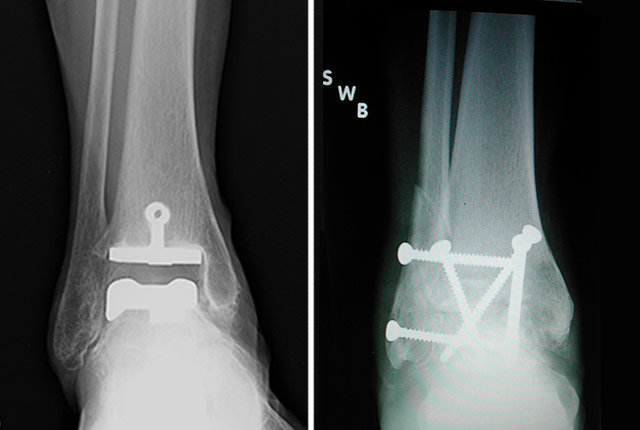

Patients with severe ankle arthritis who had total ankle replacement surgery, a procedure called arthroplasty, did better overall after two years than those that had the more traditional surgery that fuses the joint, called arthrodesis, a multi-center study led by researchers at the University of Washington School of Medicine and Puget Sound Veterans Affairs Health System has found.

Although fusion limited ankle motion, the flexibility of other nearby joints helped to compensate for that loss of motion.In recent years, however, more patients are having a procedure in which the joint is replaced with a device that maintains much of the ankle’s movement. But despite the growing popularity of joint replacement surgery, no rigorous study had yet been done in the United States to determine which surgery yields better results.